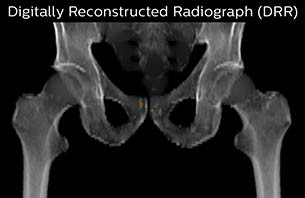

Using the mDIXON and 3D bFFE images, the RT planner marks the position of the nickel-titanium fiducial markers, and contours are transferred to the digitally reconstructed radiographs (DRRs). Reference image matching is based on these markers. “In the rare cases, where visualization of the fiducial markers fails, we do a CT to confirm their location,” Dr. Keyriläinen notes.

MR-only simulation workflow The 3D T1W FFE mDIXON sequence provides in-phase, water and fat images in one acquisition. Target and organs-at-risk are delineated on the 3D T2W TSE images. Prostate GTV is shown in orange, PTV in purple. The 3D bFFE sequence is used by the planner to mark the position of the fiducial markers (gold anchors) and contours are transferred to the digitally reconstructed radiographs (DRRs).

Based on the 3D T1W mDIXON images, MR-based density maps (MRCAT) are automatically generated. The VMAT (Volumetric Modulated Arc Therapy) plan is generated in TPS, based on MRCAT as primary image set. During the commissioning phase, dosimetric agreement between MRCAT-based and CT-based dose plans was studied and differences in the PTV dose were found to be minimal (<1% for most patients). Average difference in PTV mean values was 0.8% over the study group (n=62).